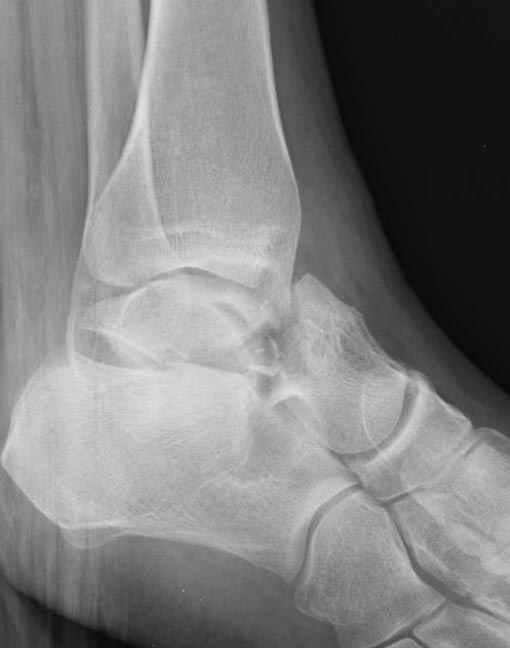

Вдогонку по поводу перелома таранной кости, больная 81, не страдает диабетом, перелом закрытый, в первый же день поступления ограничились временным наружным фиксатором (как на снимке).

Планировалась открытая фиксация после спадения отека, но больная пожелала лечиться по месту жительству в другом штате..

Примеры на снимке...